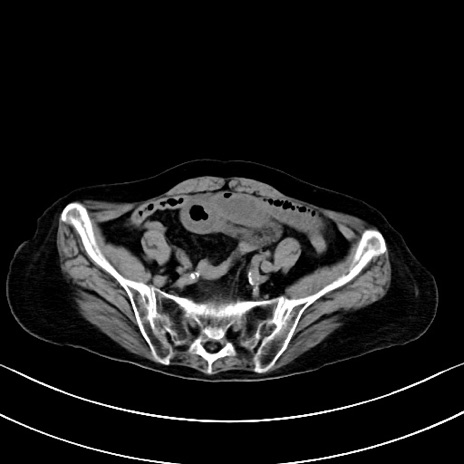

横断像

他院CT